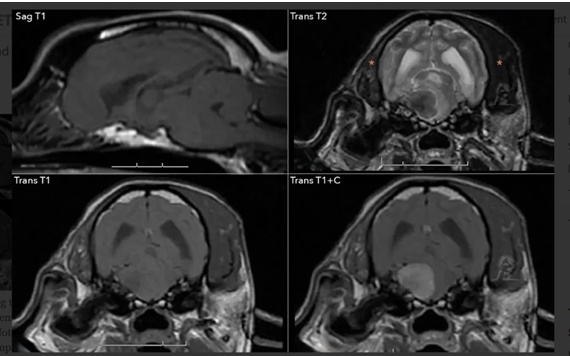

Τελευταίες έρευνες έχουν δείξει ότι σε περίπτωση απεικόνισης στην MRI αλλοίωσης στο τρίδυμο νεύρο συχνά συνυπάρχει ασυμπτωματική συλλογής υγρού στο μέσο ους από την ίδια πλευρά. Υπάρχει υποψία ότι οφείλεται σε διαταραχή της νεύρωσης του τείνοντος την μαλθακή υπερώα μυός (tensor veli palatine muscle) (από τον κάτω γναθικό κλάδο του τρίδυμου νεύρου) με συνέπεια αδυναμία διάνοιξης της ακουστικής σάλπιγγας (Eustachian tube) και μειωμένη παροχέτευση του μέσου ωτός.

Η απεικονιστική εξέταση επιλογής είναι η MRI του εγκεφάλου.

Το νεόπλασμα του ελύτρου του τρίδυμου νεύρου απεικονίζεται ως διόγκωση του νεύρου ή ως εστιακή μάζα στο επίπεδο της γέφυρας από όπου το τρίδυμο νεύρο εξέρχεται του εγκεφάλου. Το νεόπλασμα απεικονίζεται με σήμα ίσης ή μεγαλύτερης έντασης στην Τ2 ακολουθία, με σήμα ίσης έντασης στην Τι ακολουθία και παρουσιάζει ήπια ως μεγάλη απορρόφηση σκιαγραφικού στην Τ1 ακολουθία. Στην ανωτέρω MRI απεικονίζεται έντονη ατροφία του δεξιού κροταφίτη μυός σε σύγκριση με την αριστερή πλευρά.